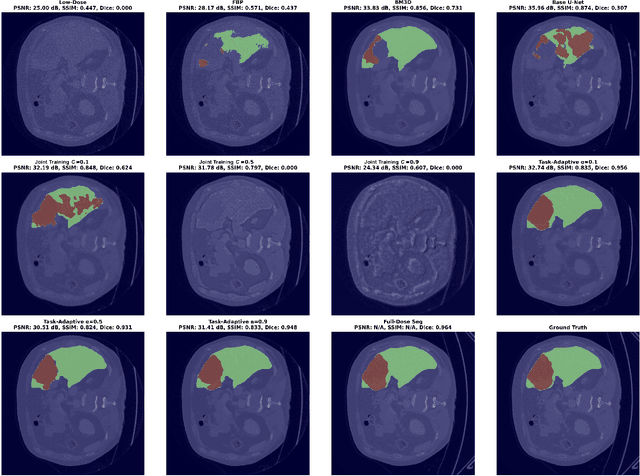

Deep learning-based low-dose computed tomography reconstruction methods already achieve high performance on standard image quality metrics like peak signal-to-noise ratio and structural similarity index measure. Yet, they frequently fail to preserve the critical anatomical details needed for diagnostic tasks. This fundamental limitation hinders their clinical applicability despite their high metric scores. We propose a novel task-adaptive reconstruction framework that addresses this gap by incorporating a frozen pre-trained task network as a regularization term in the reconstruction loss function. Unlike existing joint-training approaches that simultaneously optimize both reconstruction and task networks, and risk diverging from satisfactory reconstructions, our method leverages a pre-trained task model to guide reconstruction training while still maintaining diagnostic quality. We validate our framework on a liver and liver tumor segmentation task. Our task-adaptive models achieve Dice scores up to 0.707, approaching the performance of full-dose scans (0.874), and substantially outperforming joint-training approaches (0.331) and traditional reconstruction methods (0.626). Critically, our framework can be integrated into any existing deep learning-based reconstruction model through simple loss function modification, enabling widespread adoption for task-adaptive optimization in clinical practice. Our codes are available at: https://github.com/itu-biai/task_adaptive_ct